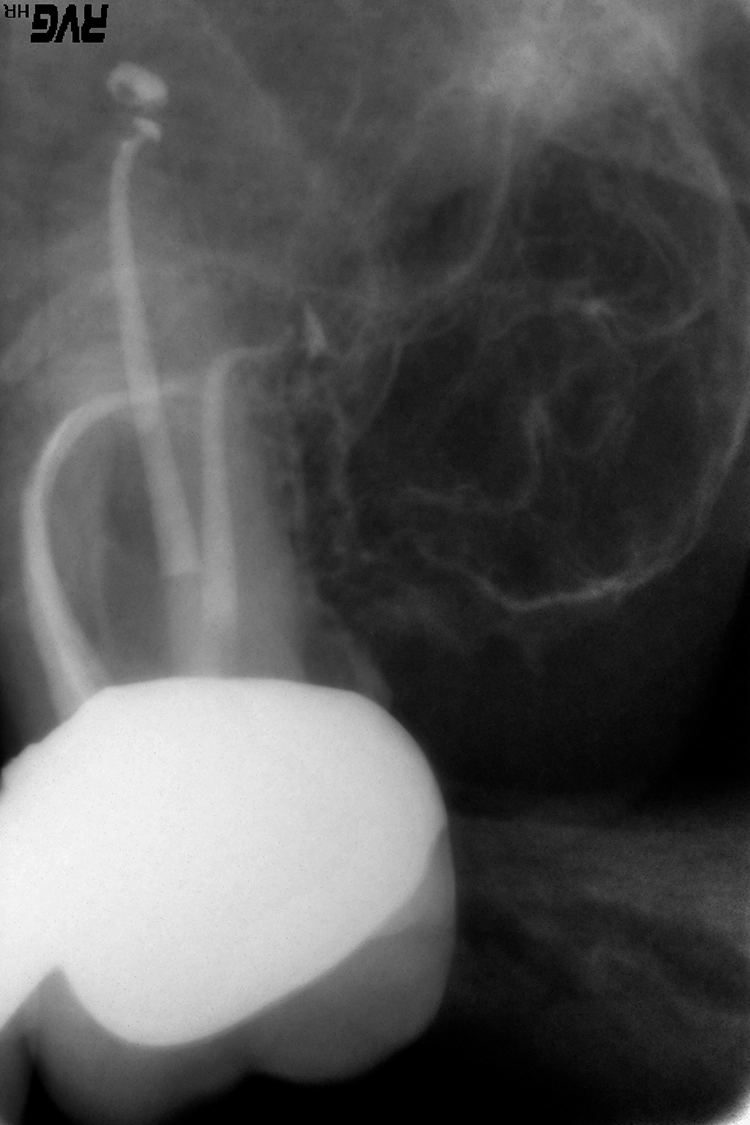

Deutlicher zeitlicher Mehraufwand liegt häufig in prozessualen Fehlern, wie bspw. übermäßigem Zahnhartsubstanzabtrag, begründet. Dieser kann zu Kanalverlagerungen und -perforationen führen (Abb. 3a und b), die ein erhöhtes Risiko für anschließende Wurzellängsfrakturen sowie den Verlust des Zahnes darstellen können [12].

Die diagnostische Grundlage für eine sichere Lagebestimmung und Abschätzung der Zugänglichkeit des zu entfernenden Instrumentenfragmentes stellt eine zweidimensionale intraorale Röntgenaufnahme (Zahnfilm) dar, die bei Bedarf durch eine 2. Aufnahme aus einer alternativen Projektionsrichtung ergänzt werden kann. Im Ausnahmefall ist eine dreidimensionale Darstellung (DVT) hilfreich.

Im 1. Behandlungsschritt erfolgt die Korrektur der vorliegenden primären Zugangskavität (Zugang zur Pulpakammer) mit dem Ziel, einen geradlinigen Zugang zum Wurzelkanallumen sicherzustellen. Dieser Behandlungsschritt ist die Voraussetzung dafür, dass auch im mittleren bzw. apikalen Wurzeldrittel verbliebene Fragmente visuell dargestellt werden können. Im 2. Schritt wird der Zugang zur koronalen Bruchfläche des Fragmentes hergestellt.